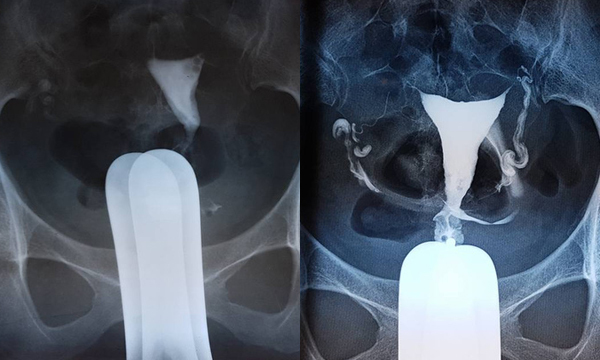

| Hình ảnh vòi trứng bị tắc (trái) và sau khi thông bằng phương pháp mới |

Ca mới nhất thực hiện ngày 6/4 phức tạp hơn, ngoài nong đoạn kẽ tử cung, bác sĩ còn phải cắt đoạn tắc sau đó nối thông vòi trứng lại với nhau như xông săm xe đạp.